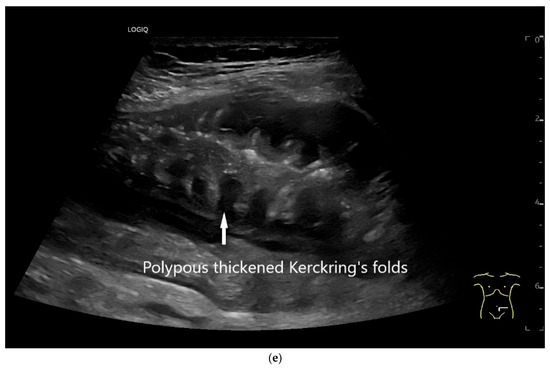

Figure 22.

Jejunal wall hematoma with a Quick ratio <5%. Smoothly defined, distinct wall thickening and lumen obstruction. The wall stratification is indistinct, slightly hyperechoic, and clearly blurred and unfocused (a). The Kerckring folds are thickened and also very blurred (b).